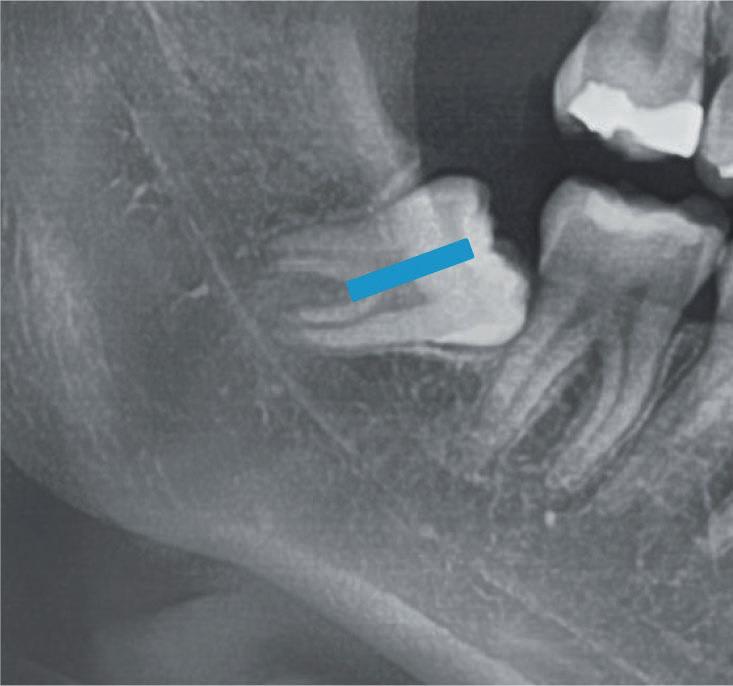

Questo è un paziente di 22 anni ed essendo un amico, ho potuto ben documentare il caso con il suo consenso: il suo dente del giudizio inferiore sinistro è stato estratto utilizzando il manipolo dritto. Figg. 143-149

Figg. 143-149 - Caso 1, paziente di 22 anni: tecnica di estrazione con divisione orizzontale utilizzando il manipolo dritto. Fig. 143 Fig. 144 Fig. 145 Fig. 146 Fig. 147 Fig. 148 Fig. 149

Il seguente caso chirurgico è di un 4.8 mesio-inclinato e parzialmente incluso. Dopo un’incisione a busta, il

dente è stato separato al centro per fare una coronectomia, prima della porzione distale e successivamente della porzione mesiale. Facendo leva quindi è stato possibile rimuovere le radici unite. Figg. 165-172

Dalla radiografia (Fig. 166) sembrava che il dente avesse due radici separate, quindi è stato eseguito un taglio orizzontale utilizzando il manipolo dritto per sezionare il dente a metà. Tuttavia, la corona si è frat-

turata poiché in realtà le radici erano unite e il dente non è stato sezionato completamente.

Bisogna prendere in considerazione sempre molti fattori come, ad esempio, la forma delle radici, il sottosquadro nella regione distale del secondo molare e l’osso alveolare disto-vestibolare. Se necessario la corona e le radici vengono separate intenzionalmente per estrarre il dente, proprio come in questo caso.